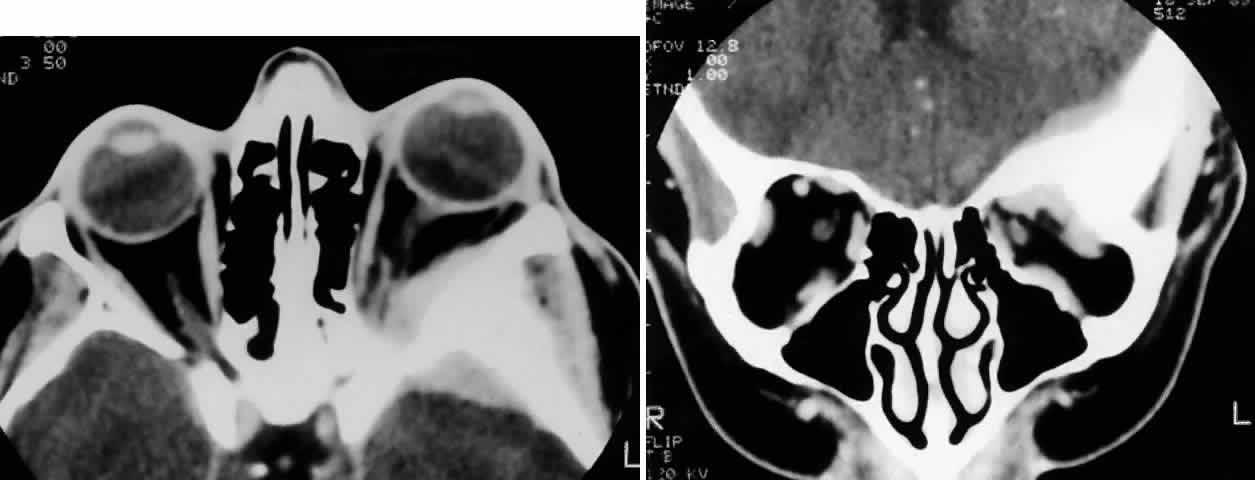

The initial clinical appearance is a whitish, rough, dry, irregular leukoplakic lesion or a telangiectatic, gelatinous, epibulbar mass. In rare instances, these tumors may be papillary, exophytic, or fixed to the underlying sclera. When confined to the conjunctiva, it can masquerade as conjunctivitis.90 The usual course is superficial invasion and slow growth because the majority are welldifferentiated tumors. It can be a locally aggressive tumor and invade intraocularly in less than 10% of cases.91 In about an equal percentage of cases, orbital invasion or nodal metastases may occur. Orbital invasion may be heralded by the development of a mass lesion with fixation of the globe. In addition, because these lesions develop insidiously, patients may present with apparent orbital cellulitis92 or draining fistulas (Fig. 10). Orbital invasion may follow multiple attempts at excision. In underdeveloped countries, higher rates of orbital invasion and metastases have been noted because of late presentation.93 Even with orbital invasion, death from metastases is exceedingly rare.

Fig. 10. A 61-year-old man presented with a chronic draining fistula (arrow) of the left lower lid and medial canthal region. It was associated with limitation of abduction, a palpable mass in the inferomedial orbit, and a papillary reaction of the medial conjunctiva(inset). Coronal CT scan demonstrates an inferomedial infiltrating orbital mass. On biopsy, it proved to be a poorly differentiated squamous cell carcinoma arising from the mucous epithelium of either the conjunctiva or lacrimal sac. The patient refused exenteration and underwent radical radiotherapy (60 Gy in 25 fractions over 5 weeks). Seven years later, he remained free of disease, although the radiated eye is scarred and shrunken. (Rootman J, Ragaz J, Cline R, Lapointe JS: Metastatic and secondary tumors of the orbit. In Rootman JR (ed): Diseases of the Orbit: A Multidisciplinary Approach, pp 405–427. Philadelphia, JB Lippincott, 1988.)